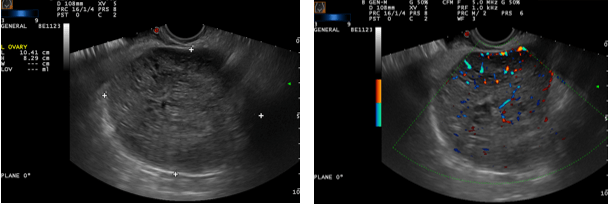

The photos below show several different types of ovarian masses:

These photos taken during a transvaginal ultrasound show a solid mass in the left ovary about the size of a grapefruit. The right photo adds color Doppler to the examination and shows that the mass is full of blood vessels. These findings are, unfortunately, most often found in an ovarian malignancy. This mass proved to be a granulosa cell tumor in this young lady.